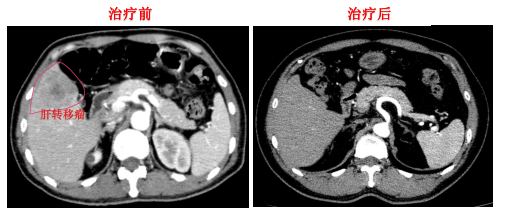

肺癌、乳腺癌、胃癌、结直肠癌等恶性肿瘤的规范化治疗和个体化治疗,擅长CT或超声影像导引下的肿瘤穿刺和物理、化学消融治疗。

典型案例